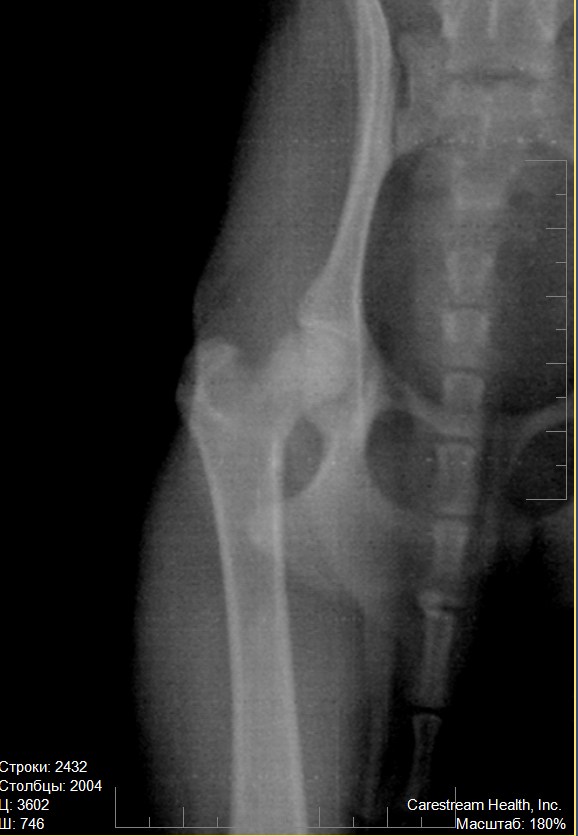

Обнаружено при осмотре: объём движений в правом ТБС ограничен, мышечный корсет атрофичен. При проводке хромота опирающейся конечности. При максимальных отведениях назад правого ТБС острая боль.

Заключение: перелом по вертлужной впадине правого ТБС

Вот теперь более-менее понятна картина. По перечисленным симптомам очень похоже на болезнь Пертеса, или остеохондропатию головки бедренной кости. На снимке явно заметна деформация головки правого сустава, левый в порядке: круглый, ровный, гладкий. Трещины на правом не видно, поэтому я бы не стала исключать другой диагноз. Врачу, конечно, виднее, но снимки можно показать и другому специалисту и выслушать его мнение. Пертес часто ошибочно связывают с травматикой, в то время как заболевание имеет наследственный характер и чаще ему подвержены мелкие породы собак. Подробнее - в интернете, а мне больше нечего добавить. Надеюсь, собачка получит своевременную помощь и лечение.

на всякий случай приложу ещё два увеличения

на всех снимках слева - правая нога

Lika-MV, к сожалению, Вы оказались абсолютно правы: это болезнь Пертеса. Причём, врач предположил это сам, после осмотра, ещё до того, как сделал снимки, несмотря на то, что заключение центровета было "трещина".

Снимков делали два, но второй снимок аж три раза: всё время Скобелева качество не удовлетворяло. Диагноз подтвердился: "асептический аваскулярный некроз головки правой бедренной кости"